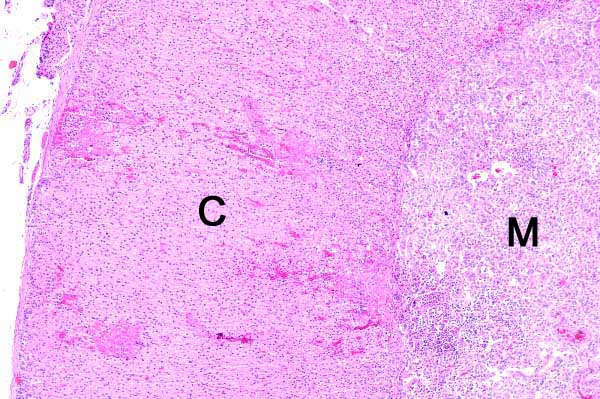

Within the cortex (C) and the medulla (M), there are small, intensely eosinophilic areas, often adjacent to a cellular infiltrate.